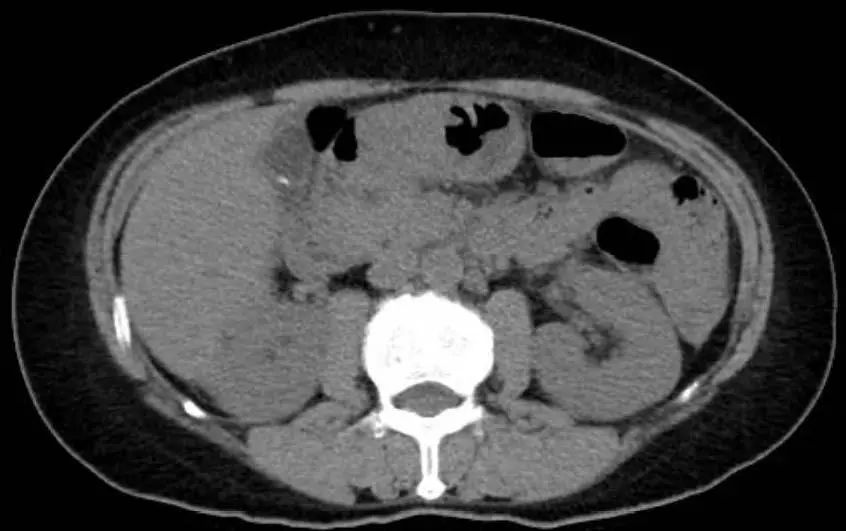

CT显示门静脉周围水肿伴有胆结石,无胆管扩张(图1)。

图1 CT示门静脉周围水肿伴胆结石